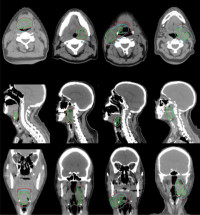

Engineers at the centre have taught a computer how to detect tiny specks of lung cancer in CT scans, which radiologists often have a difficult time identifying.

The group fed more than 1,000 CT scans - provided by the National Institutes of Health through a collaboration with the Mayo Clinic - into the software they developed to help the computer learn to look for the tumours.

LaLonde taught the computer how to ignore other tissue, nerves and other masses it encountered in the CT scans and analyse lung tissues.